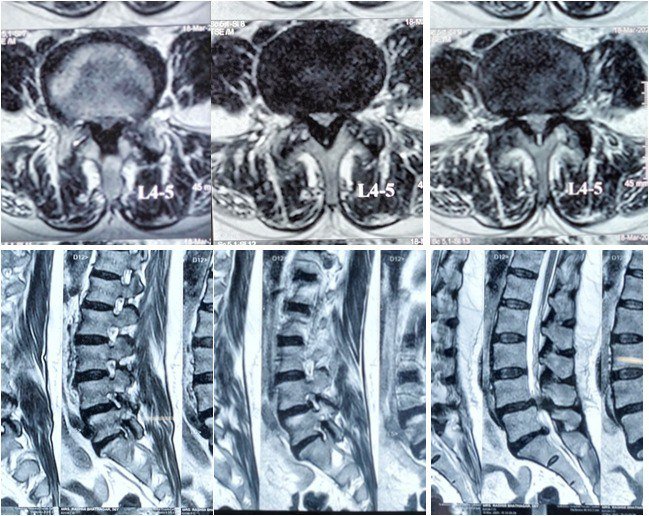

How Is Lumbar Canal Stenosis Diagnosed?

Accurate diagnosis requires correlation of symptoms with imaging findings.

- Clinical examination: Assessment of gait, reflexes, strength, and posture

- MRI lumbar spine: Gold standard to visualize canal narrowing and nerve compression

- X-rays: To assess alignment and instability

- CT scan: Helpful in evaluating bony stenosis in selected cases